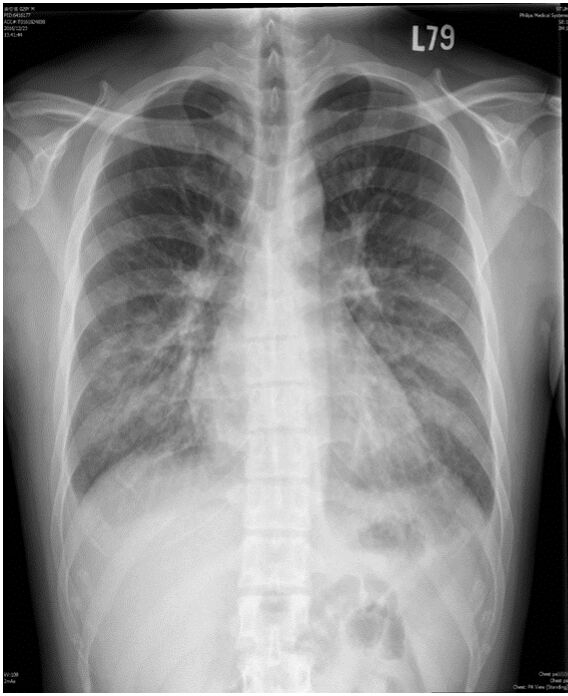

4. 病人是位29歲男性電子工程師派駐中國深圳,三個星期來,時有間歇性發燒及逐漸性呼吸困難,先在深圳 門診求醫,初以為一般感冒治療,後以支氣管炎診斷治療罔效,乃急回台灣求醫。經檢查,意識: E4M6V5; BP: 122/75 mmHg; PR: 116/min; RR: 21/min; Temperature: 37.6℃; SPO2: 94%(room air) 頸靜脈不怒張,未有貧血,胸部呈現瀰漫性濁音,心臟擴大,有Grade III/VI Diastolic murmurs at left upper sternal border,無肝脾腫大,無腹水。皮膚未有紅腫或出血斑點。2016/12/23心電圖及胸部X光如 圖。其血液、尿液及生化如次:Hemograms: WBC, 13.54(k/uL); RBC, 4.74(M/uL); Hb, 13.0 (gm%); HCT,40.2(%); MCV, 84.8 (fL); MCH,27.4(pg); Platelet,329 (k/uL); Seg, 81.5(%); Eos, 0.2(%)。尿檢: 正常。請 問這位年青病人的最可能診斷是: